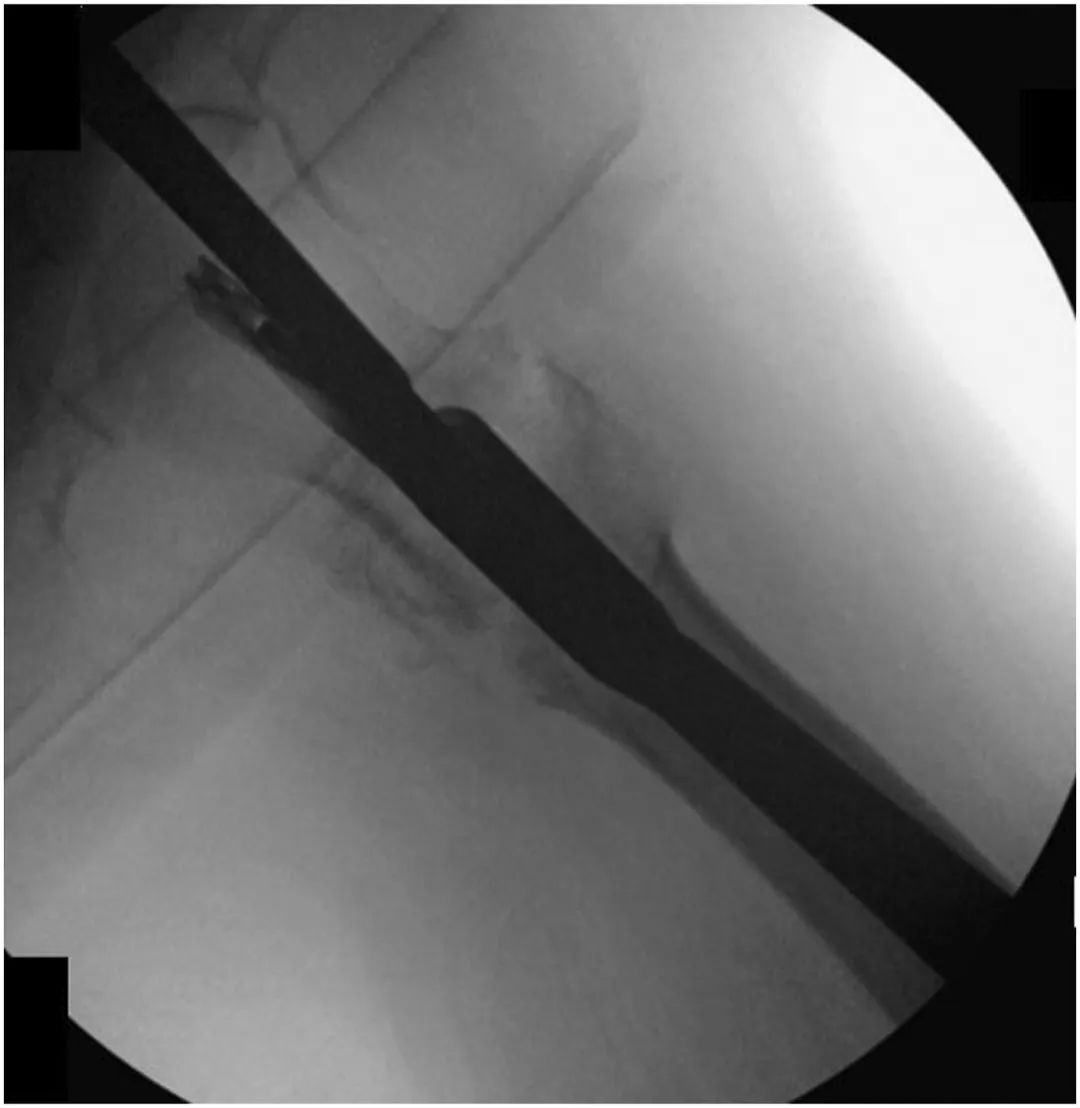

Пациентам, получившим начальную фиксацию с помощью CMN, мы выполнили модифицированную замену головки гвоздя и армирование костным цементом.Первоначально был сделан 5-сантиметровый разрез на проксимальной стороне большого вертела, проводник был помещен в проксимальную сторону стержня, и вся кость была удалена с проксимальной стороны стержня с помощью открытого римера.Затем с помощью шестигранной отвертки ослабили фиксирующий винт в верхней части CMN (рис. 2).

Рисунок 2, интраоперационная рентгеноскопия, показывающая, как шестигранная отвертка зацепляет и ослабляет ранее прибитый установочный винт.